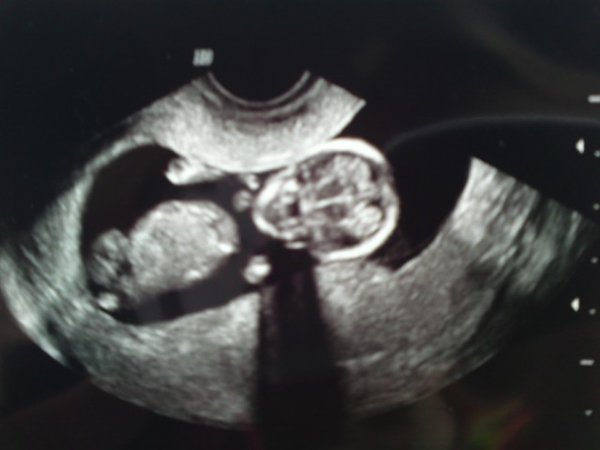

Tak Heidi:-) Ja, ja det hele så rigtig fint ud:-) Risiko 1:5799 så det er jo bare rigtig flot:-) Var bange for min alder trak NOGET længere ned......

Den var flot og fin og vendte og drejede sig, så vi rigtig ku se den

Filuca er ovenud glad og strålede som en sol da hun fik billedet:-) Ku med det samme se hvad det var! :-)